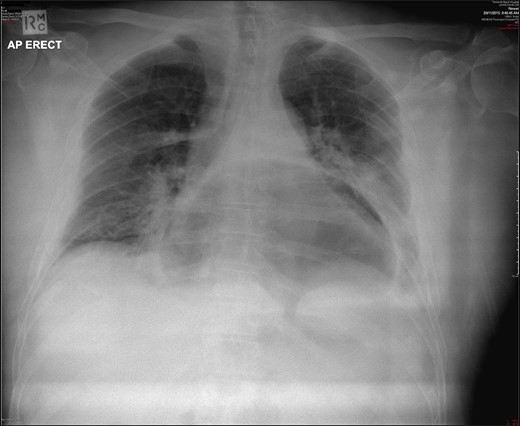

A 69-year-old man with a background medical history significant for hypertension and mild obesity, presented to his local district hospital in remote New South Wales, Australia with sudden onset of severe epigastric pain radiating to his back. He was diaphoretic and pale, and initial assessment of the patient seemed to be that of a man suffering an acute myocardial infarction. Despite this, his initial observations were all within normal limits, and his electrocardiograph revealed a sinus bradycardia and no ischaemic changes. All initial blood examinations, including serum troponin, lactate, liver function tests, renal markers, electrolytes and C-reactive protein were completely normal, with the full blood count revealing only a mild leucocytosis (12.3 × 109/L). Interestingly, the most significant finding came from his initial chest X-ray which showed a large intrathoracic gastric bubble consistent with a large hiatus hernia (Fig. 1). The patient went on to have an intravenous contrast-enhanced computed tomography (CT) scan of the chest and abdomen which revealed an obstructed intra-thoracic stomach incarcerated within a para-oesophageal hernia (Fig. 2). Surgical services in the patient’s local town are limited and thus the patient was transported to the closest regional centre with on-call general surgical services. Decompression with a nasogastric tube (NGT) was attempted but failed.

CT demonstrating obstructed intra-thoracic stomach in mesenteroaxial alignment.